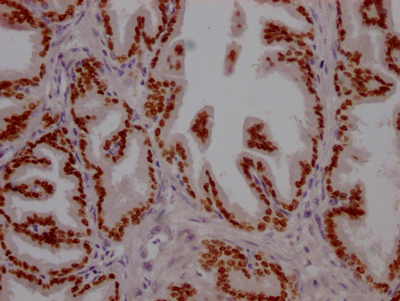

IHC image of CSB-RA246102A0HU diluted at 1:100 and staining in paraffin-embedded human breast cancer performed on a Leica BondTM system. After dewaxing and hydration, antigen retrieval was mediated by high pressure in a citrate buffer (pH 6.0). Section was blocked with 10% normal goat serum 30min at RT. Then primary antibody (1% BSA) was incubated at 4℃ overnight. The primary is detected by a Goat anti-rabbit IgG polymer labeled by HRP and visualized using 0.05% DAB.

IHC image of CSB-RA246102A0HU diluted at 1:100 and staining in paraffin-embedded human prostate tissue performed on a Leica BondTM system. After dewaxing and hydration, antigen retrieval was mediated by high pressure in a citrate buffer (pH 6.0). Section was blocked with 10% normal goat serum 30min at RT. Then primary antibody (1% BSA) was incubated at 4℃ overnight. The primary is detected by a Goat anti-rabbit IgG polymer labeled by HRP and visualized using 0.05% DAB.